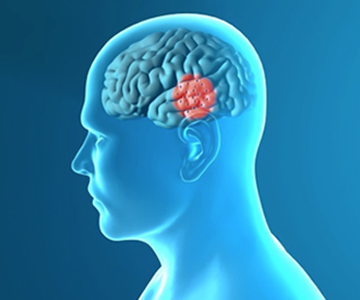

La maladie de Parkinson est liée à une dégénérescence d’une population spécifique de cellules nerveuses du cerveau : celles de la « substance noire ». Ces cellules sécrètent la dopamine et sont impliquées dans le contrôle du mouvement. Différentes stratégies de lutte contre la maladie peuvent être utilisées.

Les cellules qui dégénèrent sont les cellules de la substance noire ou « locus niger » qui est située à la base du cerveau, dans le tronc cérébral.

Les cellules de la substance noire sécrètent la dopamine qui est un neurotransmetteur et sont impliquées dans le contrôle du mouvement.

La maladie de Parkinson est la 2e maladie neurodégénérative la plus fréquente du système nerveux. Elle est due à la dégénérescence progressive d’une catégorie particulière de cellules nerveuses sécrétrices de dopamine dans le tronc cérébral (maladie « neurodégénérative »). Celui-ci se trouve sous le cerveau, en avant du cervelet et au-dessus de la moelle épinière.

Les cellules nerveuses (ou neurones) qui sont concernées sont ceux qui produisent de la dopamine dans la substance noire du cerveau (ou noyaux du « locus niger »). Or, celle-ci est impliquée dans la coordination des mouvements. La dopamine est un messager chimique (appelé neurotransmetteur), qui permet aux neurones de communiquer entre eux.

Dans la maladie de Parkinson, la production de dopamine est faible. Ce déficit provoque un mauvais contrôle des mouvements involontaires et automatiques (gestes acquis que l’on fait sans réfléchir). Ceux-ci interviennent en particulier dans la marche, les mouvements du bras et la posture, mais aussi la déglutition, le fonctionnement de l’intestin... La dopamine participe donc à toute les activités qui implique une coordination des mouvements : parler, écrire, dessiner, exécuter et coordonner un geste… La disparition des cellules nerveuses de la substance noire s'accompagne de perturbations des réseaux de neurones qui leurs sont associés dans d’autres noyaux du cerveau : le striatum, le thalamus, le noyau sous thalamique…